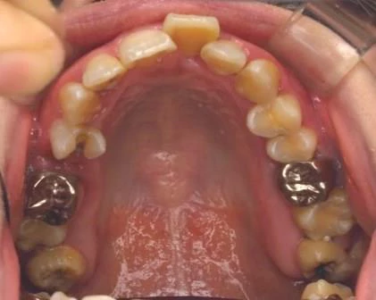

この患者さんは、前歯がでっぱで口が閉じないことを主訴に

矯正相談にこられました。

よく見ると、左下に矯正装置が一粒くっついています。

下の6番目の歯がなくなっていて、

その隣の7番目の歯が斜めにすでに倒れていました。

その歯を起こそうと、部分的に装置をつけて改善しようとしたようです。

成人の患者さんは、このように

なんらかの原因で歯をすでに失っていたり

銀歯が入っているケースが多くあります。

写真は左から 治療前→治療後→治療2年後